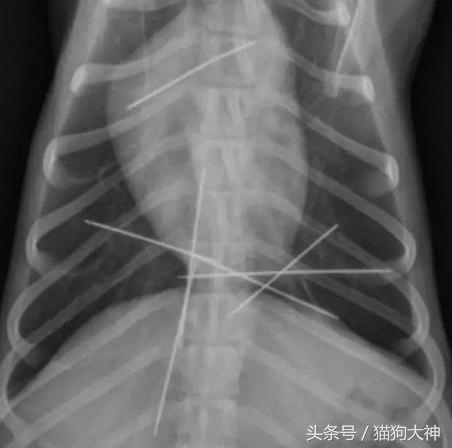

这只吉娃娃竟然吞下了九根针,主人发现时,针已经在全身上下游走,情况非常危险。